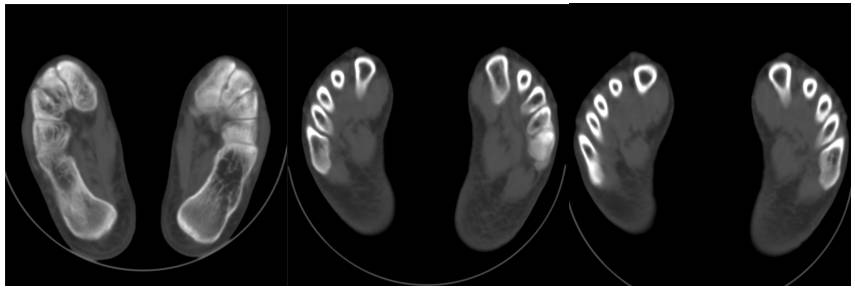

16层移动CT足部扫描